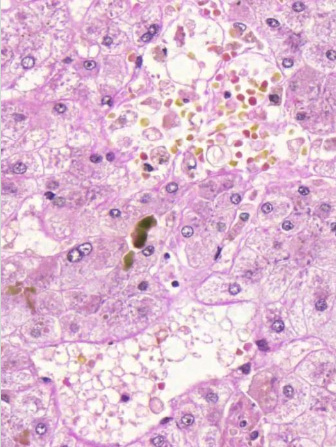

sidekudosseptoja, joiden välissä nodulaarista regeneraatiota

mitä kuvassa näkyy yleisesti ja millainen regeneraatio? (vinkki: maksaskirroosi)

hydrooppista hepatosyyttien degeneraatiota

millaista degeneraatiota kuvassa näkyy? (vinkki: maksaskirroosi)

sappistaasia

mitä on hepatosyyttien välissä? (vinkki: maksaskirroosi)

maksaskirroosi

sappitieproliferaatiota ja lievää lymfosyyttilisää